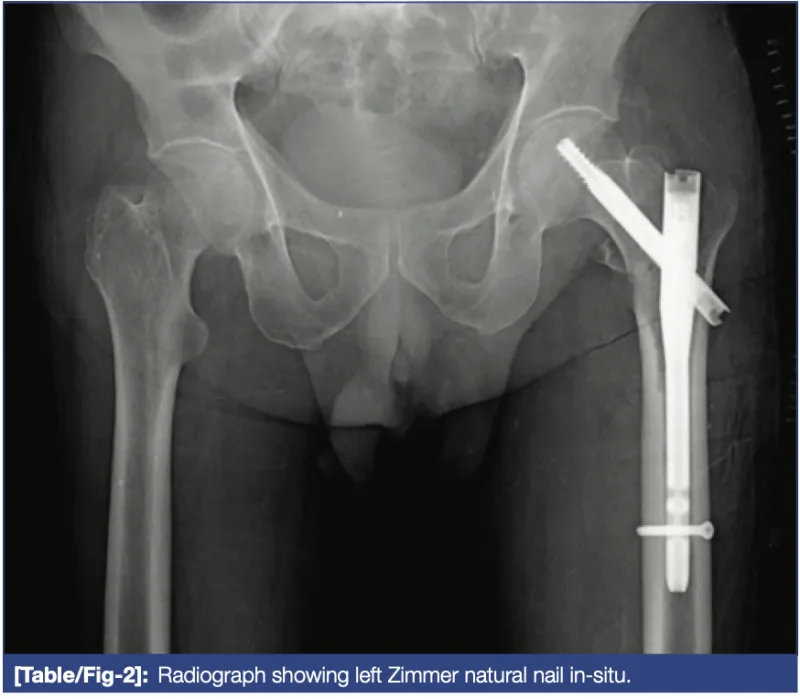

この日は, 超高齢者の大腿骨転子部骨折.

骨片は4つに分かれ, 整復には手間取りましたが, 成功.

あとは手順通りに進めて, 1時間半ほどで無事終了.